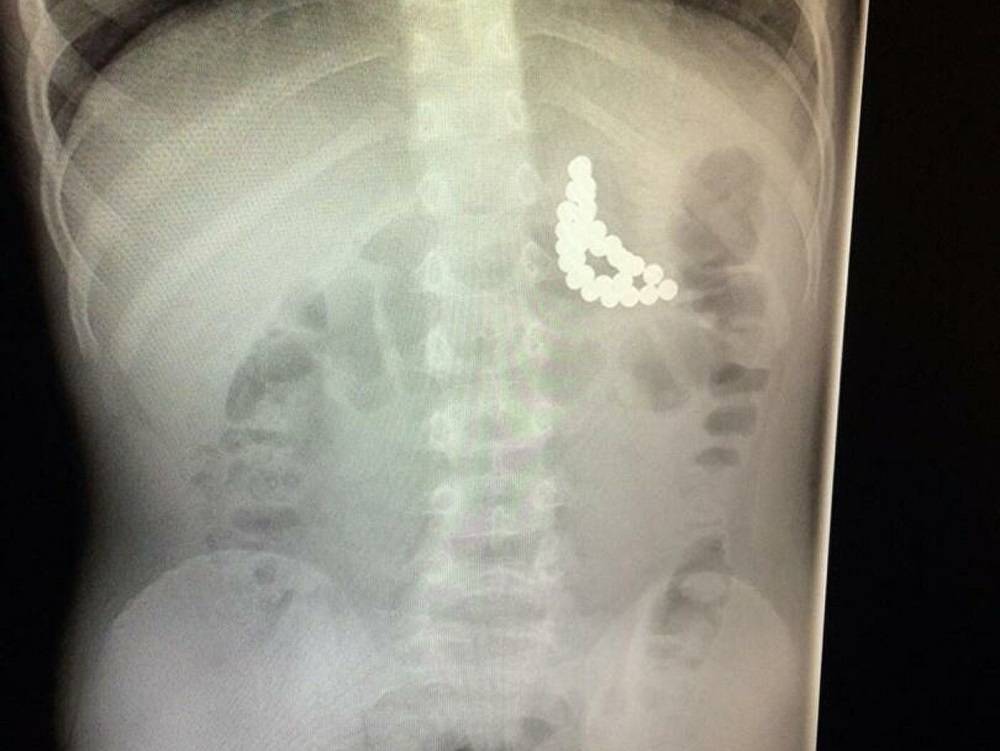

В последние 10 лет наблюдается резкое возрастание количества случаев проглатывания магнитных инородных тел; по данным американской статистики – частота обращений в экстренные медицинские службы за этот период возросла в 8,5 раз, и продолжает увеличиваться в среднем на 75% ежегодно.

В большинстве случаев, проглатывают магниты – дети младше 5 лет. Тем не менее, в последние несколько лет наблюдается увеличение частоты проглатывания магнитных шариков у детей более старшего возраста. Эти неприятные изменения связаны с увеличением производства игрушек на основе магнитных шариков, таких как Неокуб или «игрушечный пирсинг», весьма популярных среди школьников. В таких ситуациях эндоскопическое удаление магнита требовалось у 10% -12% обратившихся детей, а у 4% -5% требовались полостные хирургические операции.